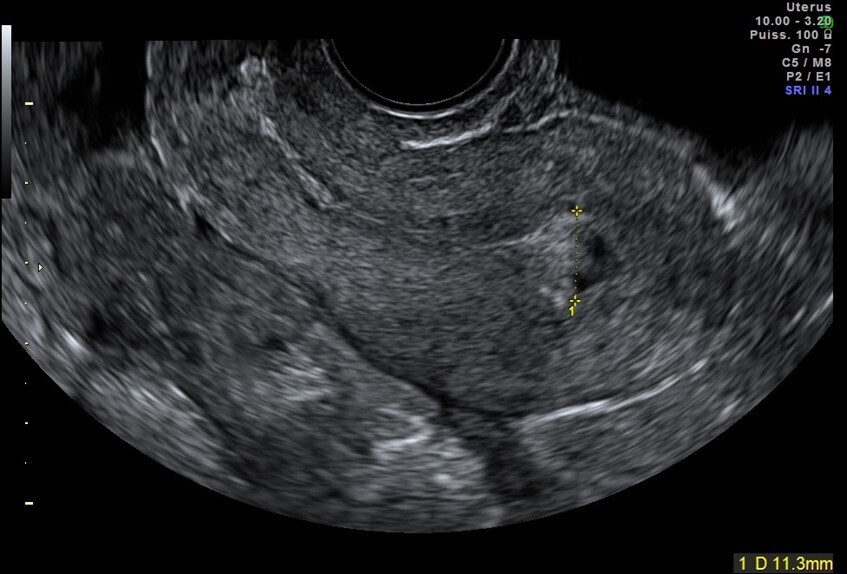

Vous faites une échographie pelvienne qui retrouve un utérus antéversé avec un endomètre épaissi de 5 mm, des ovaires droit et gauche sans anomalie. Il n’y a pas d’épanchement dans le cul-de-sac de Douglas.